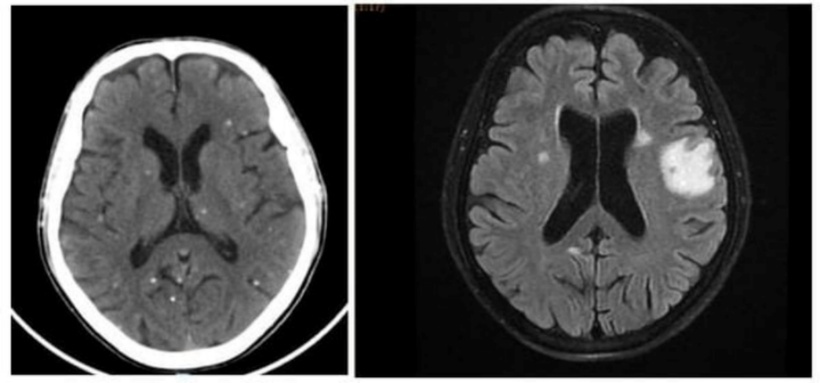

Vô số nang sán dải còn sống hoặc đã bị hóa vôi “ẩn nấp” trong não. Ảnh: BVCC.

Sau khi được thăm khám lâm sàng, bệnh nhân được chụp cộng hưởng từ (MRI) sọ não ghi nhận tổn thương não nhiều vị trí, phù não. Bác sĩ nghi ngờ bệnh nhân nhiễm ký sinh trùng ở não nên tiếp tục thực hiện xét nghiệm huyết thanh học xác nhận kết quả dương tính với ấu trùng sán dải lợn Cysticercus.

Bệnh nhân được chụp Xquang xương đùi, CT-scan ngực để tầm soát tổn thương ở cơ quan khác, phát hiện vô số nang sán dải còn sống hoặc đã bị hóa vôi “ẩn nấp” trong não, nhu mô phổi, và trong da, cơ trên toàn bộ cơ thể người bệnh.

Trường hợp này được chẩn đoán viêm não do nang sán dải lợn và nhiễm nang sán dải ở đa cơ quan, nổi bật nhất là ở não, mô dưới da và ở cơ. Người bệnh nhanh chóng được điều trị bằng thuốc chống ký sinh trùng, chống viêm, phòng ngừa co giật cùng với chăm sóc tích cực. May mắn, bệnh nhân hồi phục tốt sau quá trình điều trị và được xuất viện